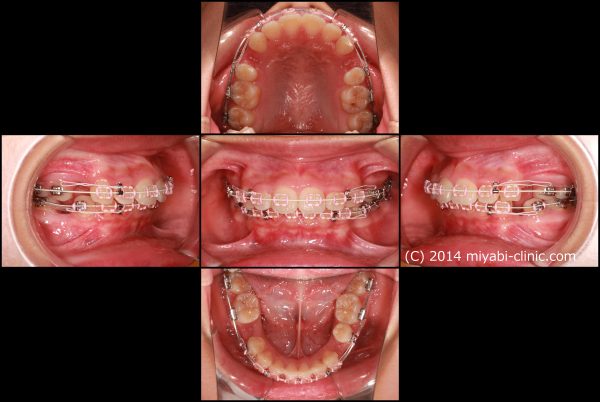

叢生を伴う 上顎前突症です

口もとの出っ張り、 前歯を下げるために上下顎左右の小臼歯抜歯を行い、前歯を後方に移動させました。

2023年7月15日にスタートして、2025年4月7日に終了しました。

治療期間は22か月でした。

抜歯を行ったことで、上顎の前後的な距離が適正になりました。

前歯が劇的に下がりましたね

同じように 下あごも前後的な距離が短くなり、適正な長さになりました。

上下歯列の長さが適正になった、この効果で上下の前歯が下がりました。

治療前後で前歯の傾斜がかなり改善しました。